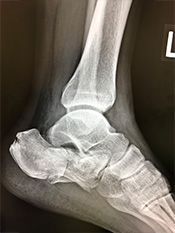

足関節骨折(足首の骨折)

疾患と症状

転倒/転落時に足をねじった場合に生じる骨折です。

多少のずれでも、骨がつくのが遅れたり、足首の障害が残ることの可能性が高い骨折のため手術を選択されることが多いものです。

• 画像:足関節骨折

(術前)